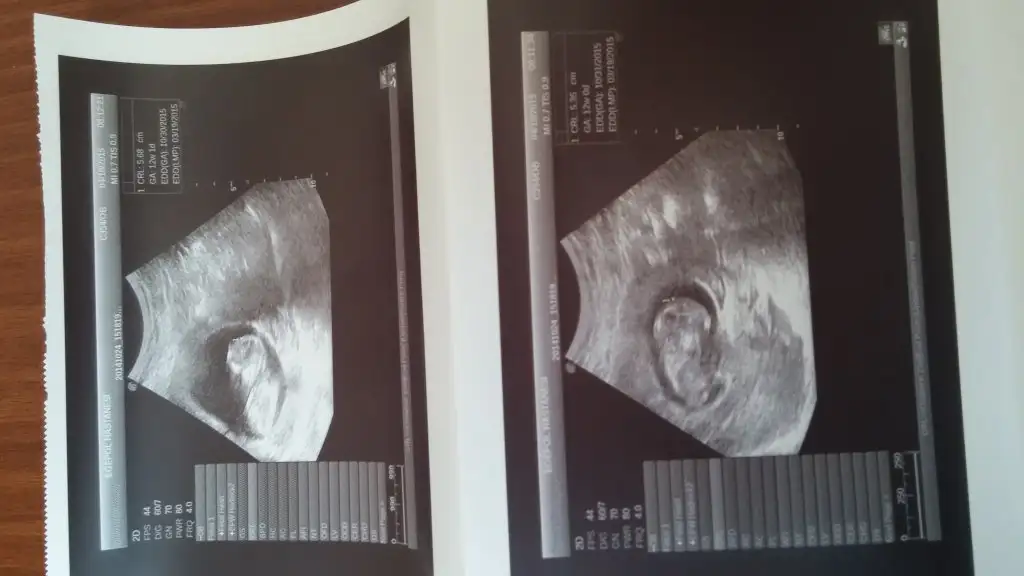

Kizlar buda arkadasimin bu sayfadan bahsedince cok merak etti bide bu resimlere yorum yaprmisiniz lütfen

Eklentiler

• image.webp

image.webp

34,7 KB · Görüntüleme: 86

30,3 KB · Görüntüleme: 95